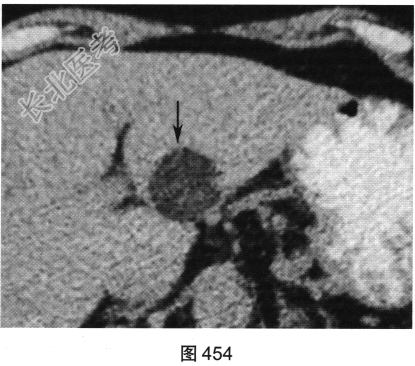

- [材料题] 患者女性,63岁,长久上腹痛并恶心、呕吐、寒战入院。超声提示肝脏有一高回声、边界清的肿块。患者进一步行肝脏CT检查,如图454~图456所示。

- 多项选择题1.对上述CT图像表述不正确的是( )

A、病灶位于肝S2/3,边界清

B、平扫病灶为低密度

C、门静脉期病灶无强化

D、动脉期病灶不均匀强化

E、动脉期病灶无强化

F、门静脉期病灶内线状轻度强化